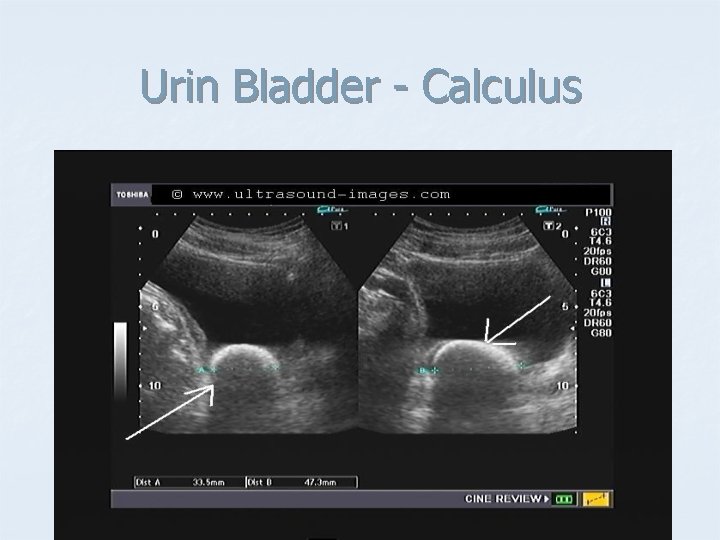

Urin Bladder - Calculus